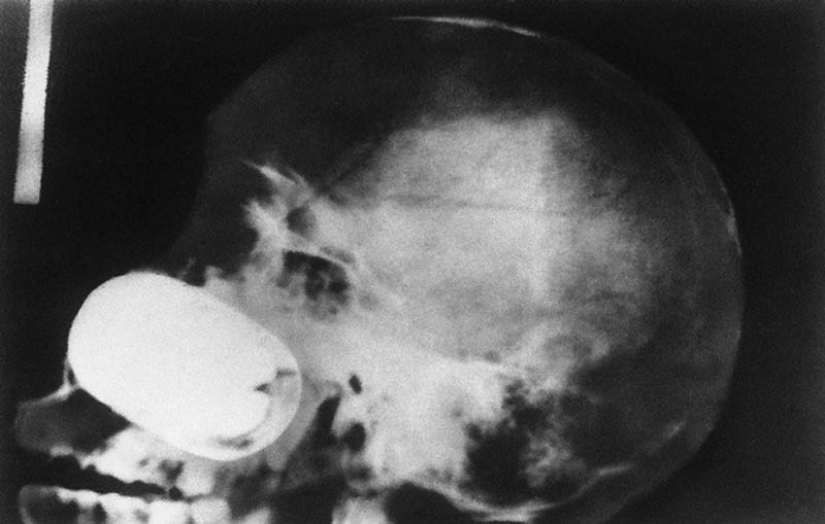

3. Vintage x-ray de el soldado de la guerra Anglo-Boer (1899-1902) con una herida de bala. La bala alojada en el metatarso entre el pulgar y el segundo dedo.